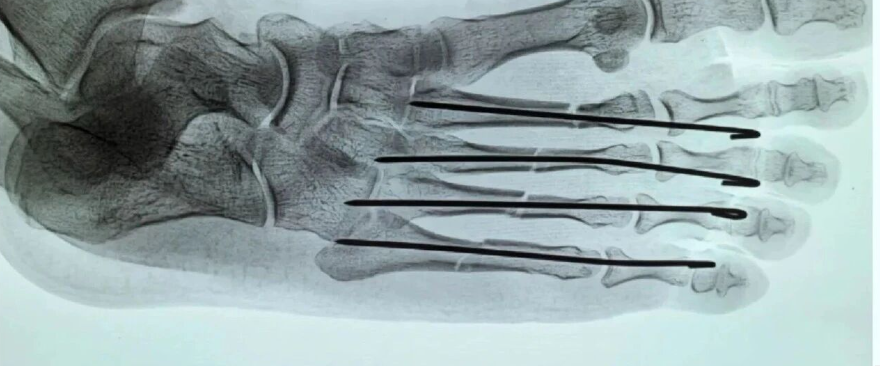

手外伤处理原则专题课程